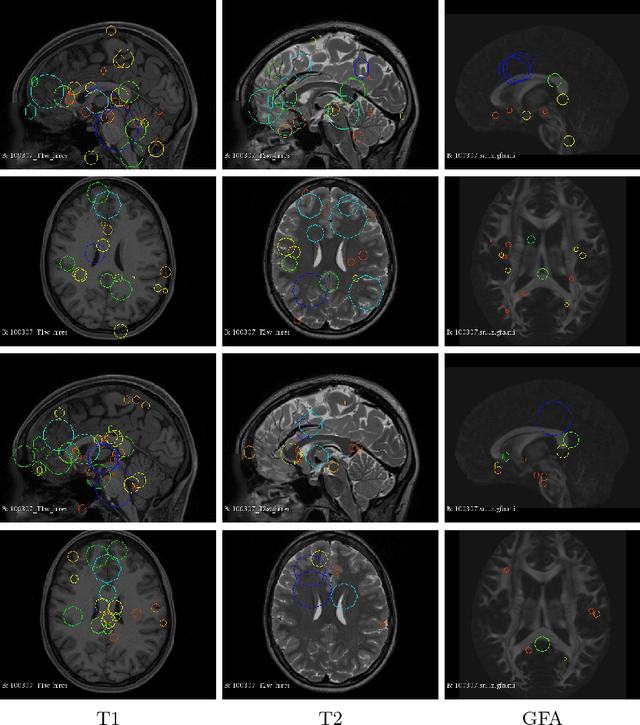

Abstract:So far, fingerprinting studies have focused on identifying features from single-modality MRI data, which capture individual characteristics in terms of brain structure, function, or white matter microstructure. However, due to the lack of a framework for comparing across multiple modalities, studies based on multi-modal data remain elusive. This paper presents a multi-modal analysis of genetically-related subjects to compare and contrast the information provided by various MRI modalities. The proposed framework represents MRI scans as bags of SIFT features, and uses these features in a nearest-neighbor graph to measure subject similarity. Experiments using the T1/T2-weighted MRI and diffusion MRI data of 861 Human Connectome Project subjects demonstrate strong links between the proposed similarity measure and genetic proximity.